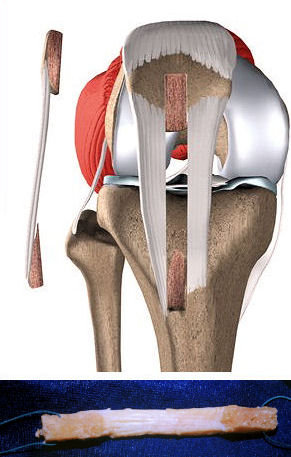

Erişkinlerde ön çapraz bağ, çoğunlukla gövdesindeki lifler ayrılıp parçalanarak yırtılır. Saçaklanmış bir doku şeklindeki bağın tamiri mümkün değildir ve ameliyat sırasında yeni bir doku ile bağın onarılması gerekir. Bağ tamiri için sıklıkla diz çevresindeki kasların kirişleri kullanılır. Bunun için en sık kullanılan doku, dizin ön kısmında yer alan ve iki ucunda kemik bloğu ile alınan patellar tendondur.

İkinci sıklıkta kullanılan doku, dizin arka kısmında yer alan ve hamstring tendonları olarak bilinen dokulardır. Hamstring tendonlarının uçlarında kemik bloğu yoktur.

Önce bağ tamirinde kullanılacak olan doku alınır, bu dokuya greft adı verilir. Daha sonra diz artroskopisi yapılarak eklem içindeki diğer yapılar değerlendirilir. Menisküs ve eklem kıkırdağında yaralanma varsa gerekli girişim yapılır. Daha sonra diz eklemindeki kemiklere tüneller açılarak, yeni bağın geçeceği yol hazırlanır. Bu tünellerin içinden greft geçirilerek uygun gerginlikte kemik tünellerin içinde tespit edilir. Bunun için metal veya eriyebilen vidalar, çapraz çiviler ve u şeklinde çiviler kullanılır. Bağı yerinde tutan bu vida ve çiviler rahatsızlık vermediği sürece ömür boyu vücutta kalabilir ve çıkartılmaları gerekmez.Video